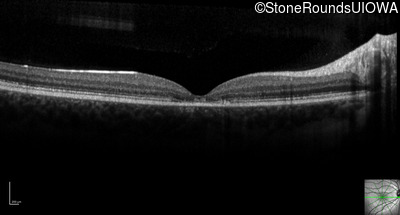

Optical Coherence Tomography - Right - 20/32

Exemplar / OCT Stack

Optical Coherence Tomography - Left - 20/50